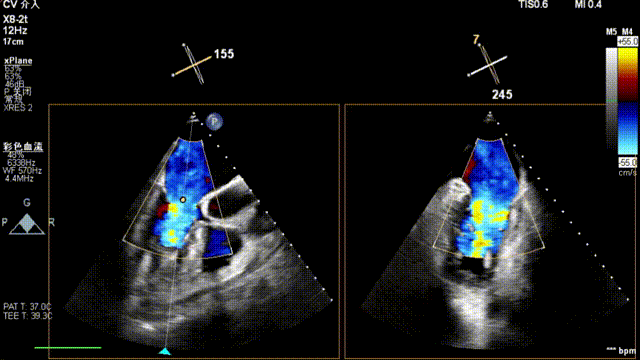

全麻后,二尖瓣夹合器系统在心前区的肋间切开3-4CM小切口,暴露心脏的心尖位置,送系统送入左心房,顺利到达病变二尖瓣区域。在经食道超声辅助下,术者通过反复评估二尖瓣反流位置、抓捕位置、反流程度,首先在2偏3区位置处于二尖瓣闭合线垂直进行巧妙夹合。在2区靠近3区位置处植入了1枚ValveClamp®MVC-IIf夹,最终评估评估反流降至轻度,平均跨瓣压差降至2mmHg,手术取得圆满成功。

术中超声(关键步骤)

术后超声

最终在A3P2位置夹合,前叶夹合量10mm,后叶夹合量8mm,剩余瓣口面积3.45cm²,平均跨瓣压差2mmHg,反流基本消除。